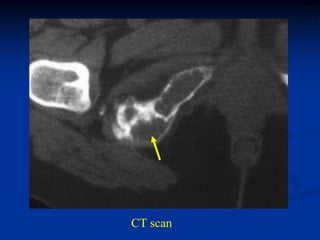

Coronal T-1 MRI

CT scan